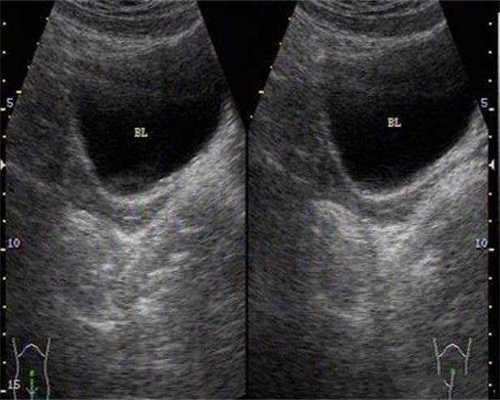

打破卵针后卵泡是否会萎缩因人而异。

由于个体差异,如年龄、体质等,可能导致卵泡对破卵针的反应不同,从而影响卵泡是否会出现萎缩现象。此外,如果在使用破卵针后未能成功受孕,也有可能会导致卵泡萎缩。为了确保卵泡的健康状态,建议定期进行妇科检查,以监测卵泡的变化情况。

如果女性存在卵巢多囊样改变或子宫内膜增生等问题,可能会导致排卵障碍,此时使用促排卵药物可能效果不佳,甚至出现卵泡不破裂的情况。